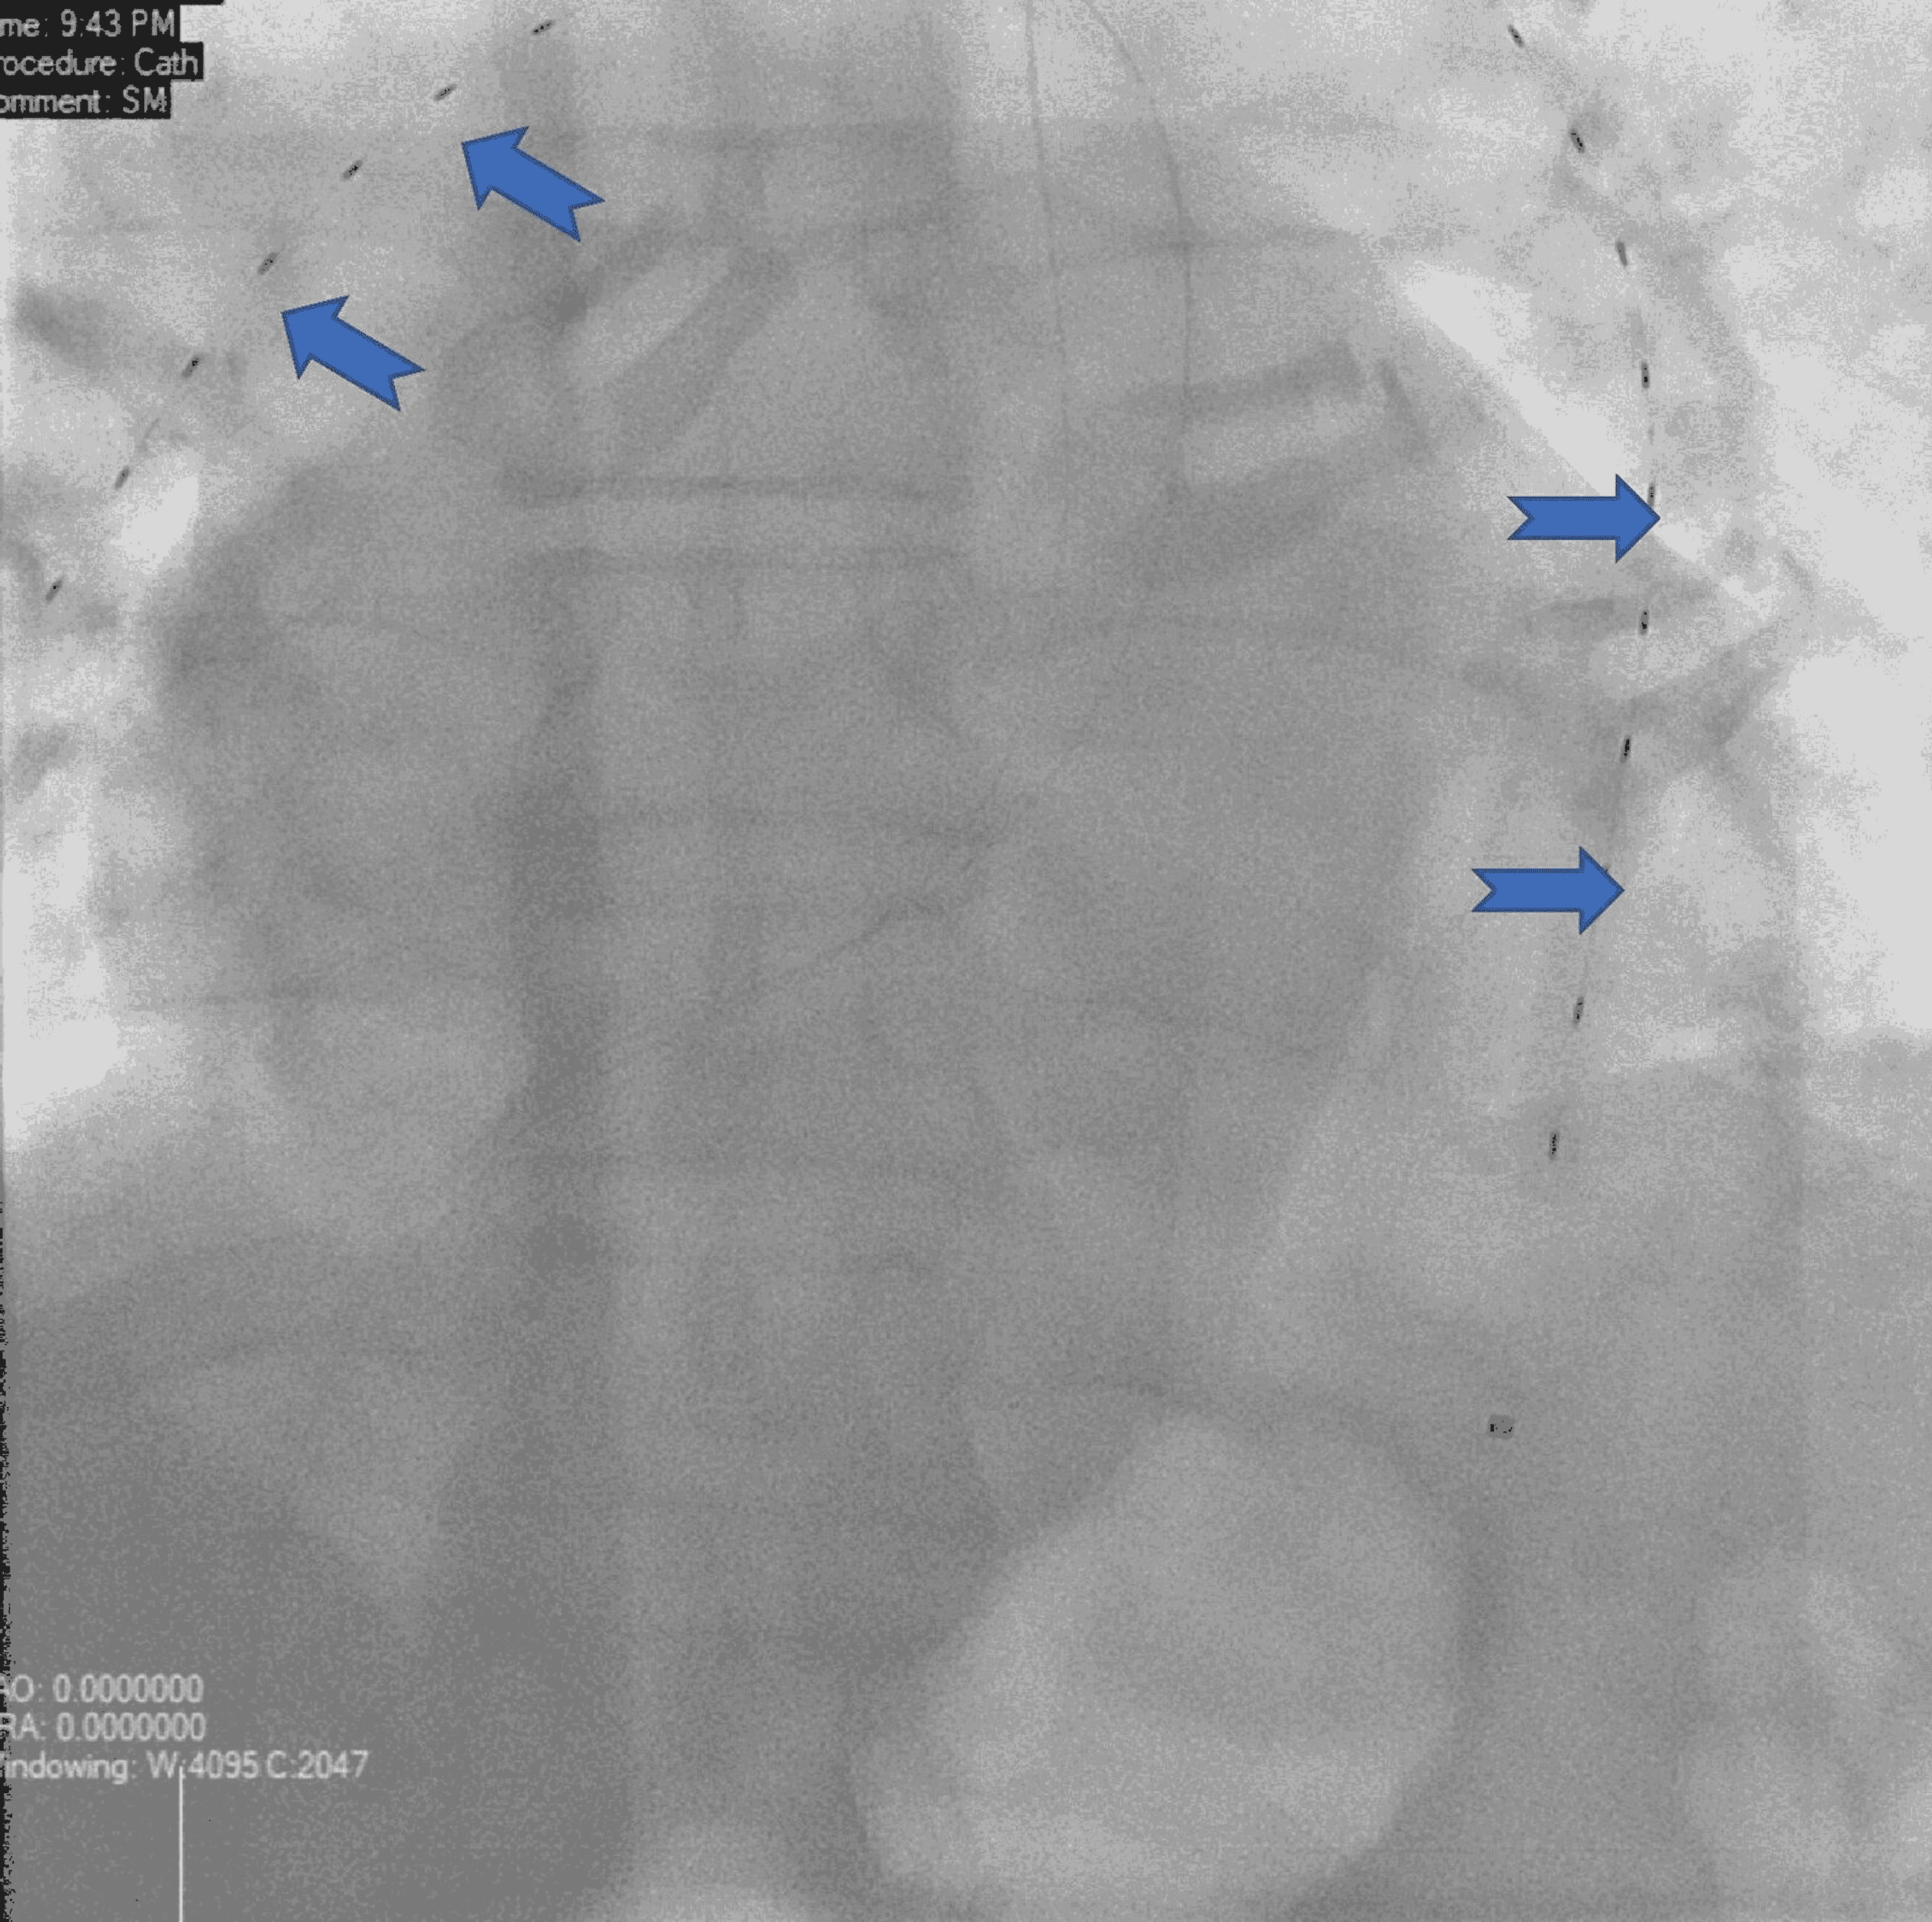

Bilateral EKOS catheter thrombolysis of acute bilateral pulmonary

Bilateral EKOS catheter thrombolysis of acute bilateral pulmonary Ekos Catheter Pulmonary Embolism Once arteriography is completed, the pulmonary catheter can be exchanged for a selective catheter to select the pulmonary branch with. Today, it’s trusted by more clinicians than any other pe. Utilization of ekos in patients with pulmonary embolism. Treating pulmonary embolism with the ekostm endovascular system: Proven to yield safe and effective results, ekos is low risk and reliable. Ekos. Ekos Catheter Pulmonary Embolism.

Bilateral EKOS catheter thrombolysis of acute bilateral pulmonary Ekos Catheter Pulmonary Embolism Utilization of ekos in patients with pulmonary embolism. Ekos was the first interventional device cleared for treating pulmonary embolism. Treating pulmonary embolism with the ekostm endovascular system: Today, it’s trusted by more clinicians than any other pe. Once arteriography is completed, the pulmonary catheter can be exchanged for a selective catheter to select the pulmonary branch with. Proven to yield. Ekos Catheter Pulmonary Embolism.